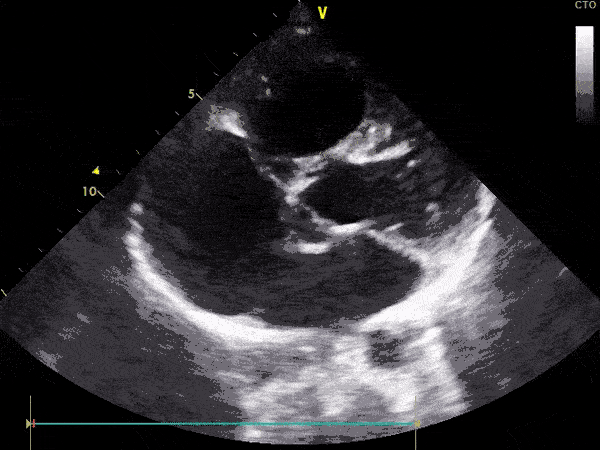

Ekokardiografia transtorakale triplex (2D, color, doppler) ose e njohur ndryshe si eko e zemrës. Ky është ekzaminimi bazë dhe i domosdoshëm për të diagnostikuar këto sëmundje.

Pamje të kapura me TTE:

Me anë të TTE-së vëzhgohen shumë mirë vrimat në zemër, duke përfshirë:

• Pozicionin e tyre.

• Madhësinë.

• Ndikimin në madhësinë dhe funksionimin e zemrës.

Me anë të TTE-së mund të vëzhgohen dhe të vlerësohen:

• Valvulat e zemrës.

• Enët e gjakut që dalin nga zemra.

• Enët e gjakut që hyjnë në zemër.

Nga rezultati i TTE-së varet edhe trajtimi i mëtejshëm i fëmijës. E rëndësishme është se sa më shpejt të diagnostikohet një sëmundje e lindur e zemrës aq më efikas është dhe trajtimi.